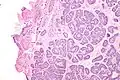

| Micrograph of a Sertoli cell nodule. H&E stain. | |

A Sertoli cell nodule is a benign proliferation of Sertoli cells that arises in association with cryptorchidism (undescended testis).[1] They are not composed of a clonal cell population, i.e. neoplastic; thus, technically, they should not be called an adenoma.[2]

Sertoli cell nodules are unencapsulated nodules that consist of:[2][3][4]

- cells arranged in well-formed tubules (that vaguely resemble immature Sertoli cells), with

- bland hyperchromatic oval/round nuclei that are stratified, and

- may contain eosinophilic (hyaline) blob in lumen (centre).